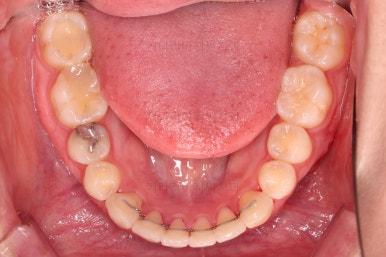

초진 시 입안의 모습을 보실게요.

결국은 앞니 사이에 틈이 생겼기 때문에 이같은 문제점을 인지하시고 내원하셨던거죠.

이번 환자분의 경우는 치아 결손 부위의 잇몸뼈도 양호했고 공간도 그리 크진 않았으며 윗니는 갯수가 1개 부족해도 교합을 맞추는데 문제가 거의 없기 때문에 시간이 좀 더 들더라도 임플란트 없이 앞니 사이 틈과 결손부위 틈새를 모아보기로 했어요.

치아 갯수 및 사이즈 문제로 위아래의 정중선은 100% 일치시키긴 힘들지만 가능한 선에서 최대한 맞추었고요.

윗니가 1개 없는 상태에서의 교합도 잘 맞추고 마무리를 했습니다.

다시 틈새가 벌어지지 말라고 유지철사를 붙여주었고요.